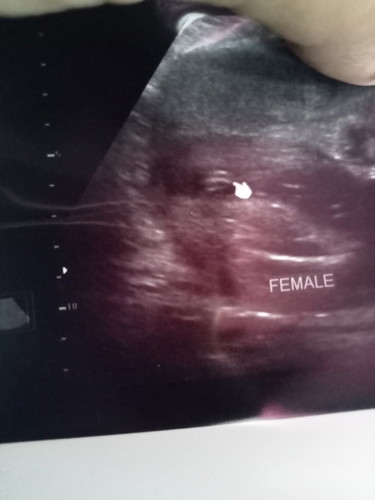

อัลตร้าซาวด์

ตั้งความหวังไว้มากว่าคนที่2จะเป็นลูกสาว ถามหมอ3ครั้งดู3ครั้งก็บอกว่าเป็นกลีบได้ลูกสาวแม่หรือใครมีประสบการณ์ช่วยดูอีกแรงคอนเฟิร์มอีกเสียงได้ไหมคะว่าเป็นกลีบได้ลูกสาวจริงไม่เคลื่อนแน่นอนแม่กังวลมากค่ะ หรือถ้าไม่ใช่จะได้ตัดความหวังไปเลยขอบคุณนะคะ